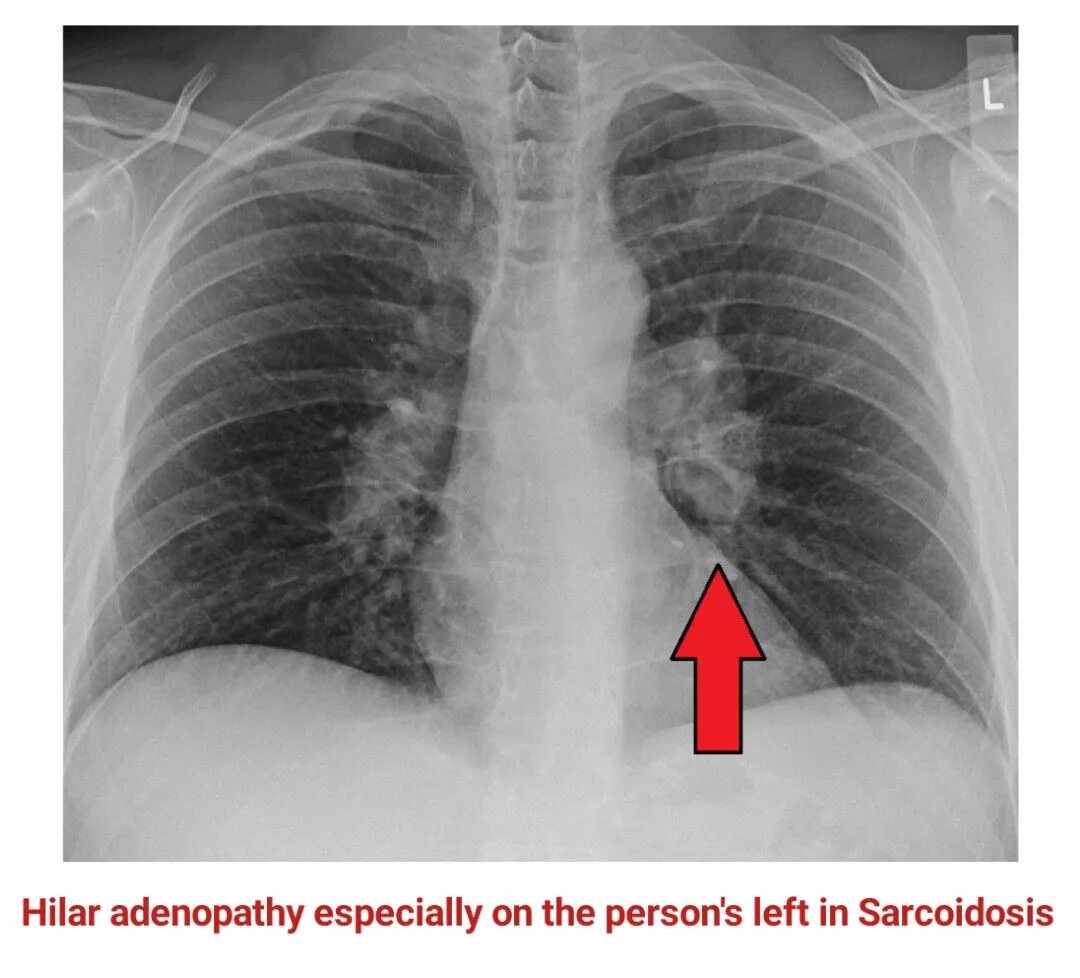

Ренген легких платно